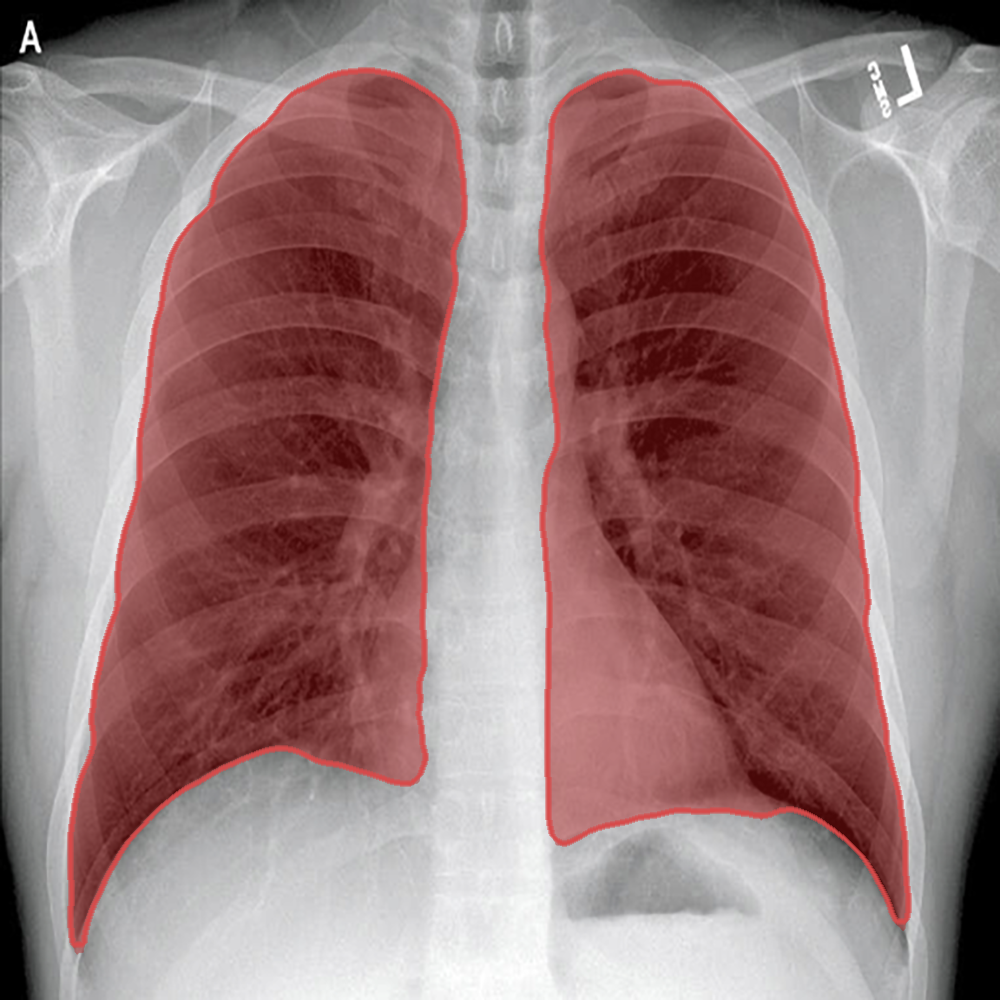

Introduction: We present a collection of lung segmentation models designed for accurate analysis of chest X-ray (CXR) images. These models have undergone rigorous training, validation, hyperparameter tuning, and testing on a diverse dataset consisting of CXRs from three publicly available sources: the Darwin, Montgomery, and Shenzhen datasets.

Dataset Description: The dataset includes CXRs from patients diagnosed with various respiratory diseases, including COVID-19, pneumonia, and tuberculosis. While these conditions differ in nature and disease patterns, we intentionally included them in the training data to improve the ability of the models to generalize across a range of pathologies. The dataset is summarized in Table 1 and publicly available at https://data.mendeley.com/datasets/8gf9vpkhgy/2.

Model Comparison: After a thorough evaluation, DeepLabV3+ emerged as our top choice. It exhibited exceptional performance with a DSCtest score of 0.963, while maintaining computational efficiency with a total of 7.4 million parameters and 2.2 billion MACs. This combination of high performance and computational efficiency solidified its position as the optimal model for our lung segmentation task.

Segmentation example - Shenzhen.png